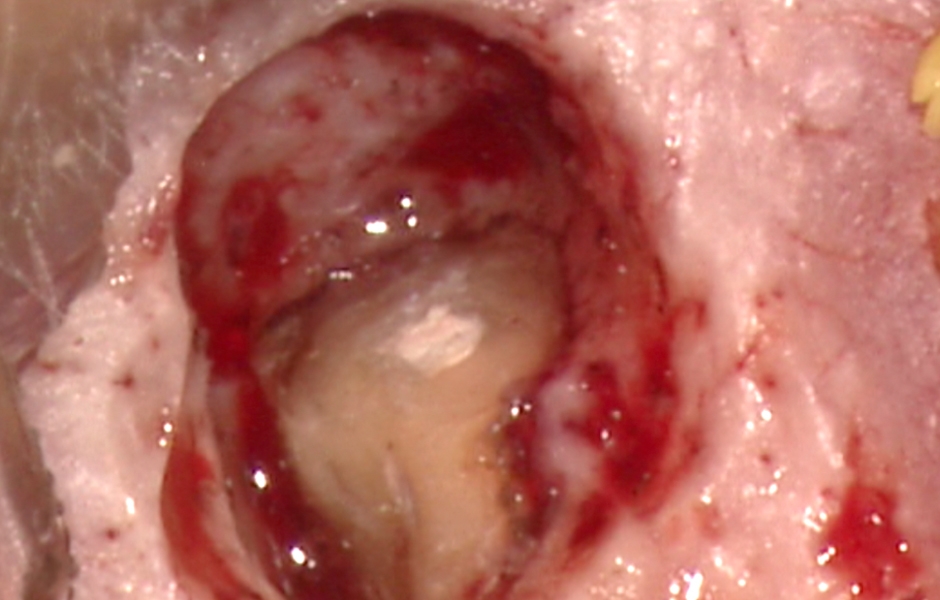

Obr. 1.2: Submarginální incize.

Obr. 1.3: Retrográdní výplň bílým MTA.

Obr. 1.5: Odstranění sutur po 48 hodinách a kontrola po třech letech – kompletní absence jizvy.